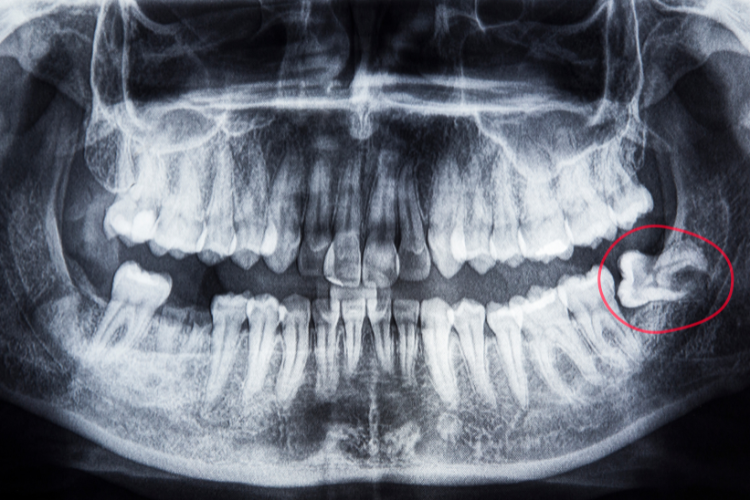

Wisdom teeth (also called third molars) usually appear between ages 17 and 25. But because our jaws are smaller than in the past, there’s often not enough room for them to come in properly.

- Partially erupted teeth (trapped under the gum)

- Risk of damaging nearby teeth or causing crowding